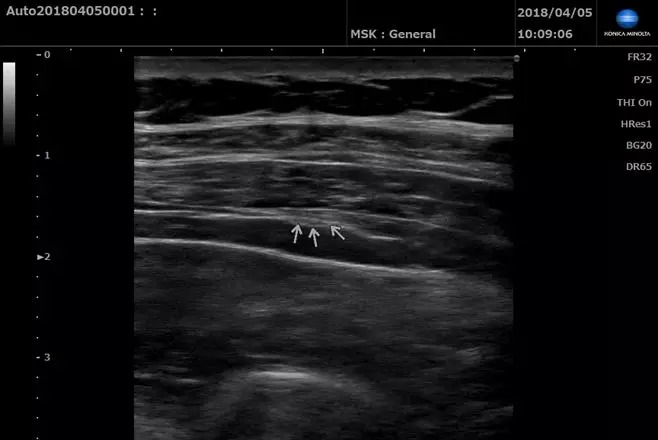

柯尼卡美能達攜明星產品SONIMAGE HS1助力Workshop環節,對肩、肘、腕、髖、膝、踝關節實際操作超聲檢查。

參會醫生學習熱情高漲,圍在帶教專家周圍,根據超聲屏幕上顯示的圖像,不斷發出提問,專家一一耐心講解。